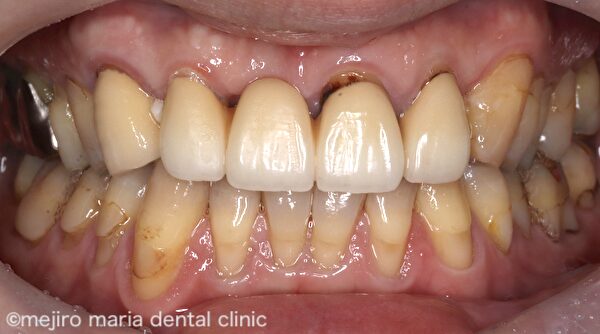

患者様は現在装着中の前歯のブリッジの見た目が悪いという点と、食べ物が詰まって困るという2点を主訴に受診されました。

右上3〜左上2までのブリッジが装着されており、欠損部である右上1の歯肉は大きく凹んでしまっています。また、歯肉に対して適合の悪いブリッジが作製されており、歯肉には著明な炎症所見が認められます。この状態では適切に清掃を行い健康な歯肉を維持することはできないでしょう。

上記Before画像を見ると、欠損部である右上1の歯肉が大きく陥凹しているのがわかります。この凹んだ歯肉に合わせてブリッジが作製されていたために機能的、審美的な障害が生じていました。